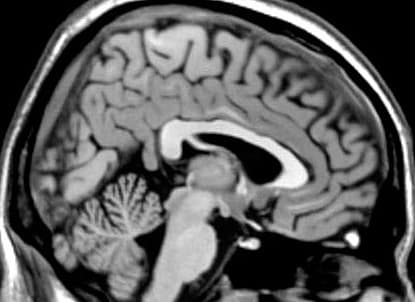

umåleligt lavt P-adrenokortikotropt hormon (ACTH)-niveau (< 1 pM), hvilket tydede på sekundær binyrebarkinsufficiens. Den øvrige hypofysefunktion var normal med normale værdier af thyroideastimulerende hormon, frit T3 og T4, prolaktin, insulin-like growth factor-1, follikelstimulerende hormon, luteiniserende hormon og testosteron. MR-skanning af hypofyse og hypothalamus viste ingen cerebral patologi. Klinisk var patienten ikke i manifest Addisonkrise og havde normalt blodtryk samt normale værdier af P-glukose, P-kalium og P-natrium. Han blev derfor sat i behandling med hydrokortison 20 mg morgen og 10 mg aften. Ved kontrol havde han dog på eget initiativ stoppet behandlingen pga. søvnløshed.

Patienten i sygehistorien havde et vægttab på 10 kg allerede seks uger efter påbegyndelse af opioidbehandlingen, hvilket er foreneligt med akut debut af binyrebarkinsufficiens, som beskrevet ved behandling med såvel tramadol [3] som morfin [4]. Ved en MR-skanning udelukkede man cerebral patologi som årsag, og tilstanden var normaliseret en måned efter ophør med opioidbehandlingen. Dette sandsynliggør opioider som årsag til patientens binyrebarkinsufficiens, da denne typisk er reversibel efter seponering af behandlingen [2]. Mekanismen for binyrebarkinsufficiens under opioidbehandling er ikke fuldt klarlagt, men den er formentlig centralt betinget [2] og skyldes til dels lavere ACTH-sekretion efter stimulering af corticotropin-releasing hormone [5].